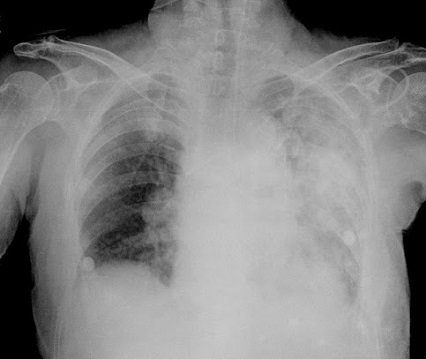

일반적으로 발열, 기침, 가래와 같은 증상이 있고

흉부 X선 사진에서 폐렴을 의심할 수 있는 소견이 나온다.

병원균성 폐렴 (pneumonia caused by pathogens)

폐렴을 일으키는 병원균에 의해

폐에 감염되는 급성 염증성 호흡기 질환이다.

주로 열과 오한 기침 가래가 나고

X-선 상에 폐렴 병변이 보인다.

진단

증상과 징후 및 배양검사 결과에 의해 진단 되지만

개개인에 따라 증상이 다른 경우가 많다.

균배양이 정확하지만

균배양은 대략 50% 정도에서만 가능하다.

정확한 진단을 위해 흉부 X-선 검사를 시행하나 폐렴 이외

다른 호흡기 질환과 감별이 필요할 때는 흉부 CT 검사를 실시하며

확실한 진단을 위해

객담검사, 혈액검사, 혈청검사, 흉막액 배양검사 등을 실시하기도 한다.